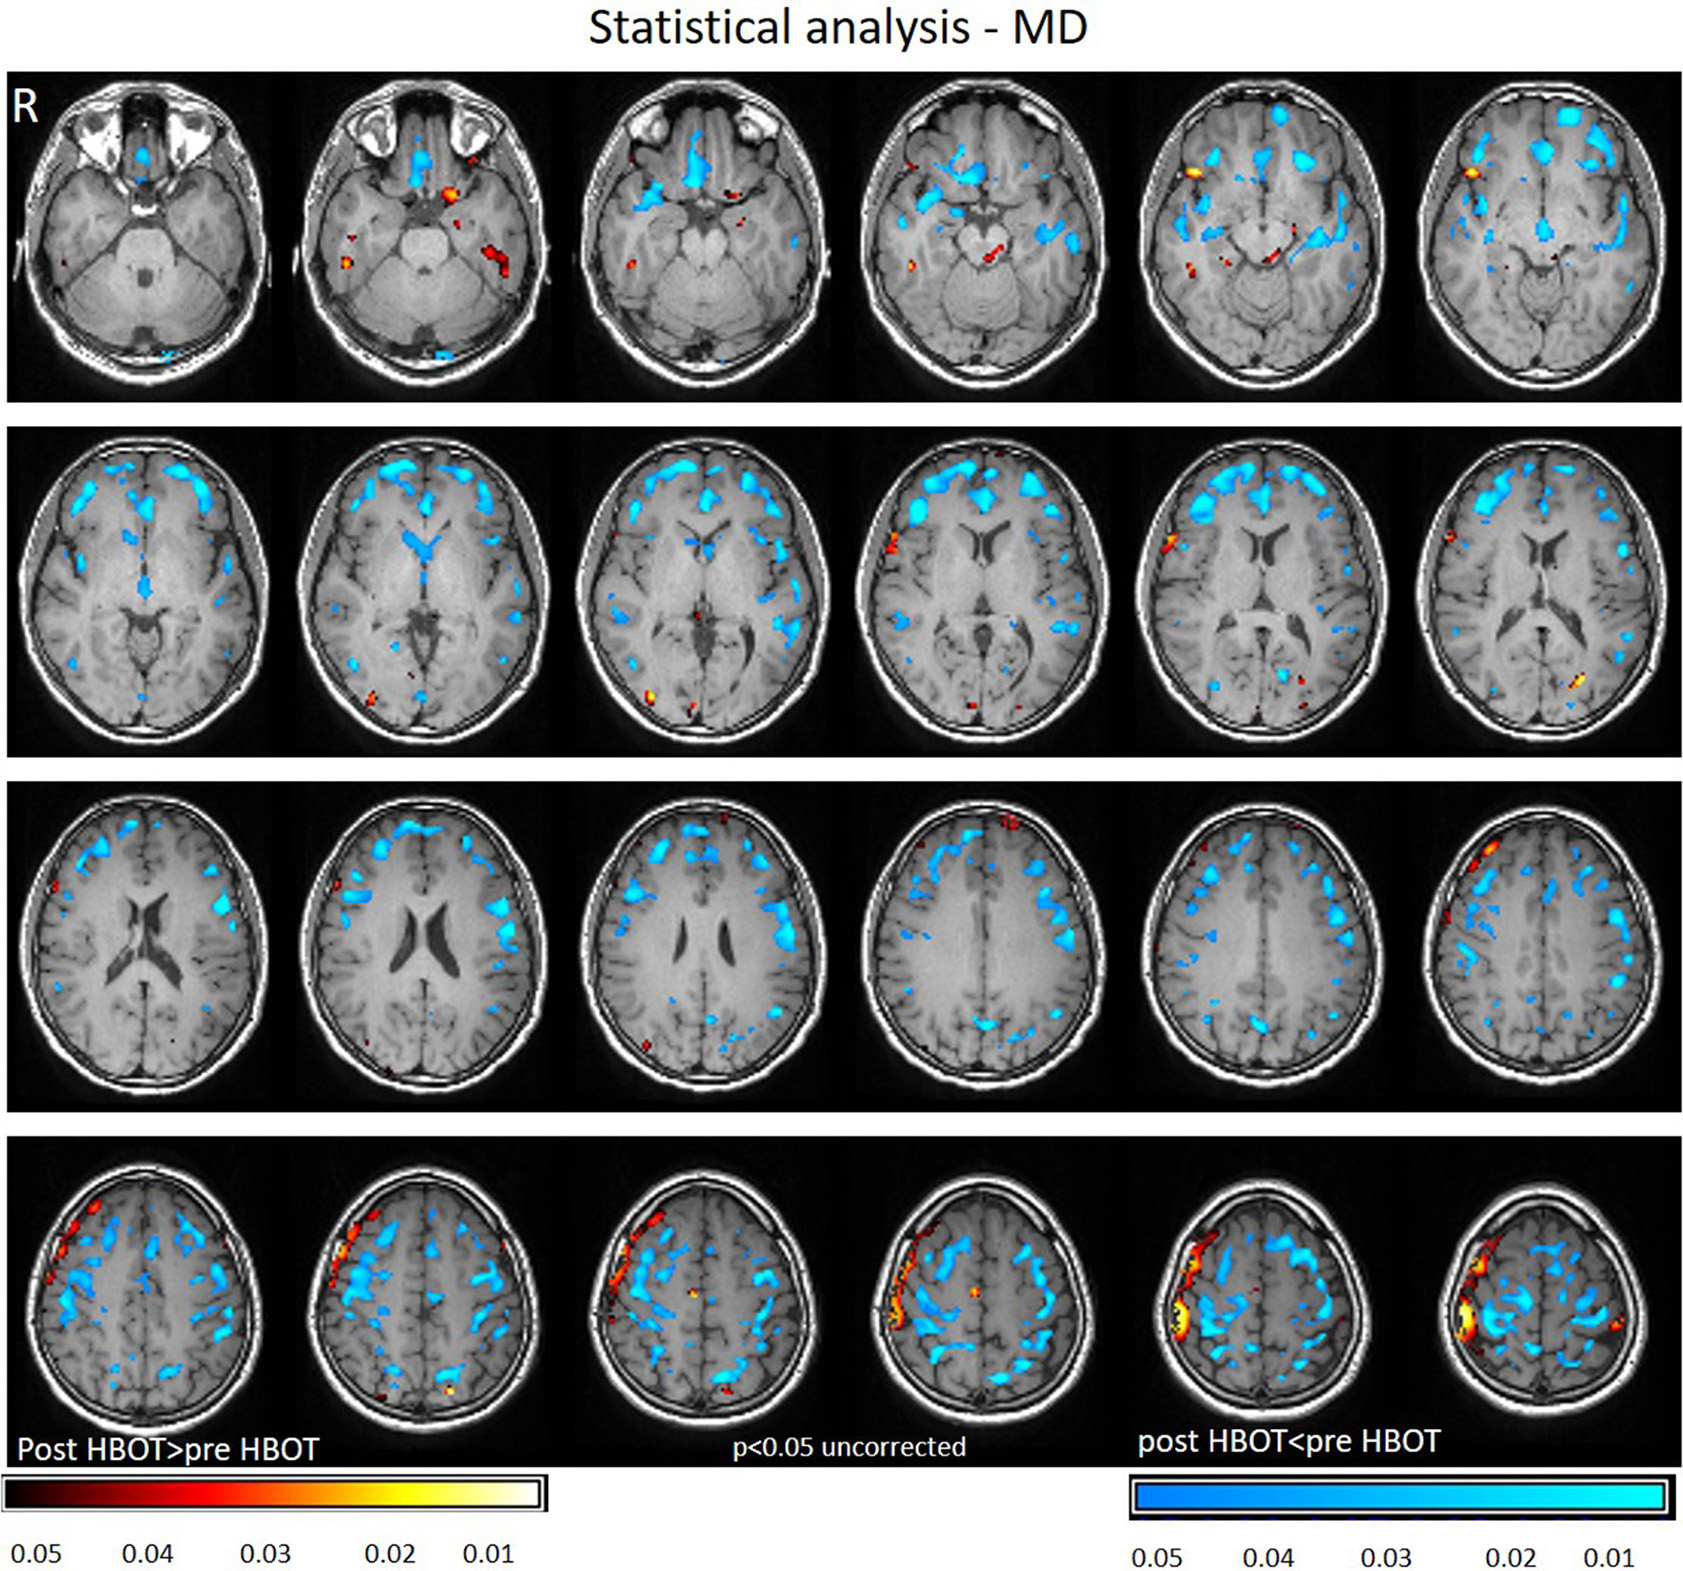

Voxel-based DTI analysis was compared before and after HBOT using paired t-test. FA and MD whole brain maps are depicted in Figures 2, 3, and show the statistically significant increase in FA (yellow in Figure 2) and decrease in MD (blue in Figure 3) average values.

Figure 3

Average DTI normalized delta change in MD maps. Blue areas mark statistically significant decrease in MD (p < 0.05).

Decrease in MD was found in the frontal lobe (anterior cingulate gyrus, posterior orbital gyrus, Precuneus, superior frontal gyrus, Uncinate fasciculus, and frontal lobe white matter, left middle frontal gyrus, precentral gyrus). Graphs of MD in significant clusters are presented in Figures 4C,D.